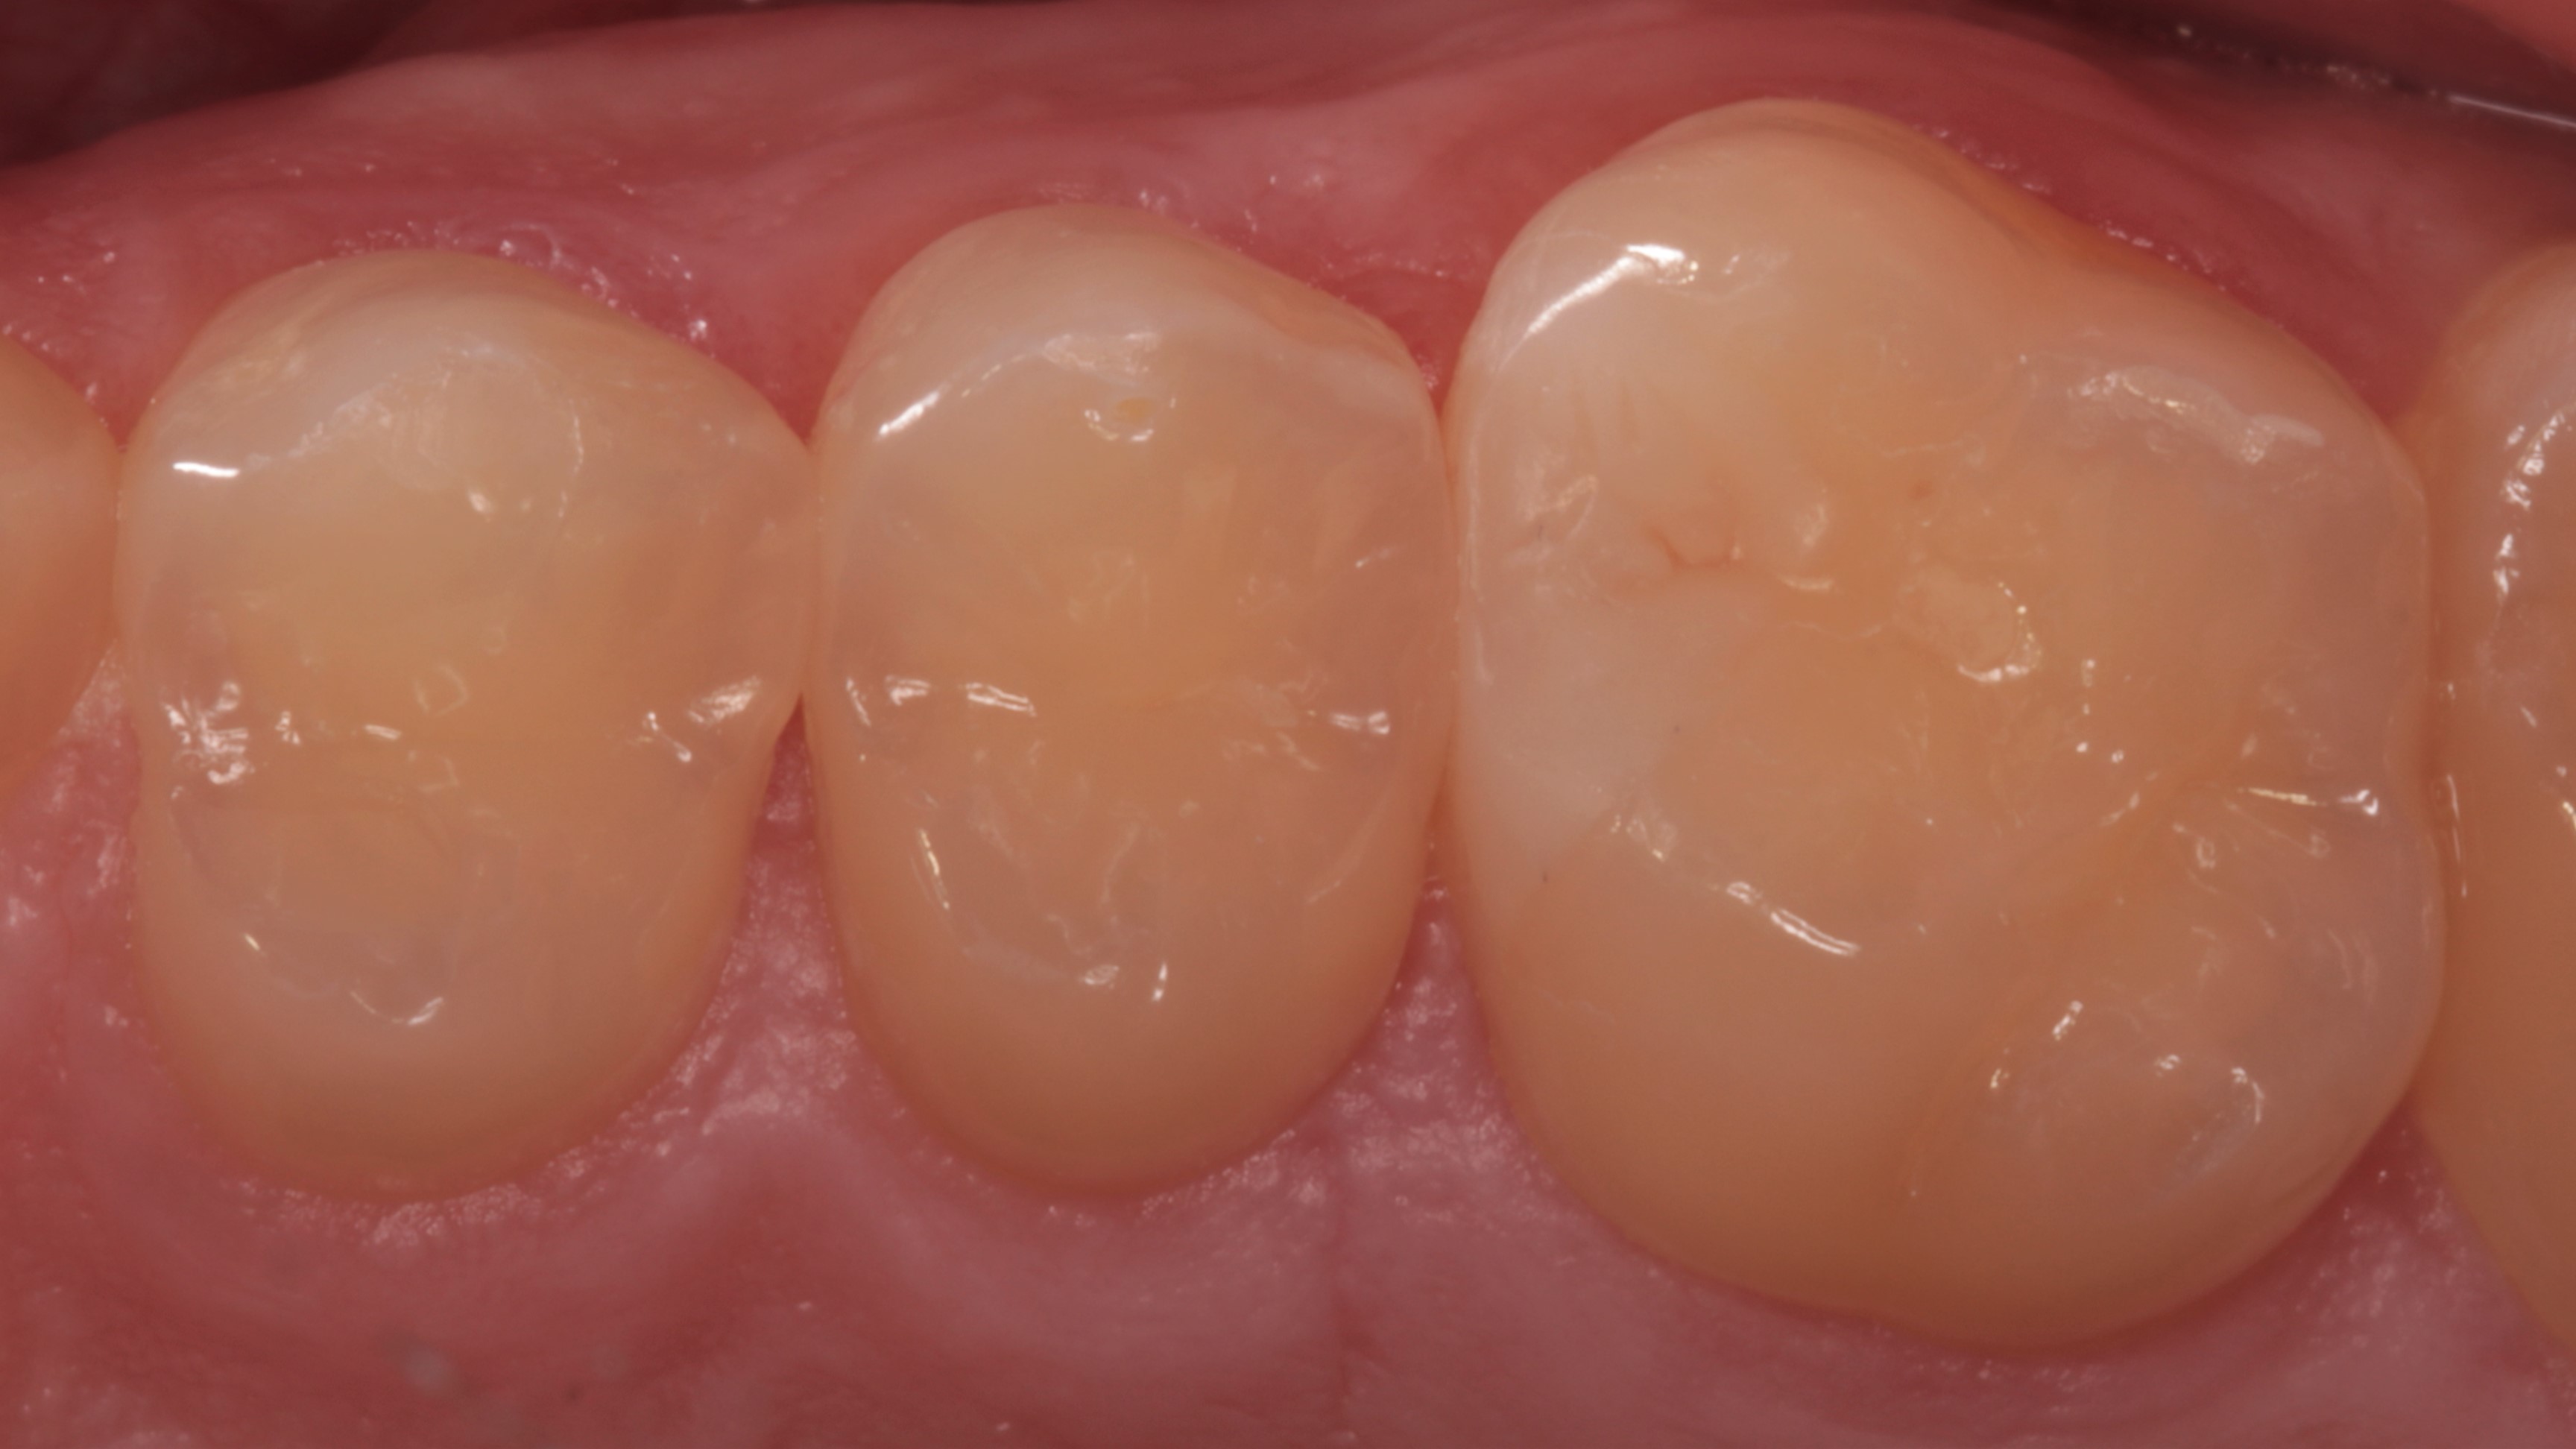

Widoczne zranienia dziąseł (ryc. 29 i 30) uległy całkowitemu wygojeniu po 3 tygodniach (ryc. 31 i 32).

Ryc. 31. Gojenie tkanek miękkich 3 tygodnie po zabiegu.

Ryc. 32. Gojenie tkanek miękkich 3 tygodnie po zabiegu – widok przedsionkowy.